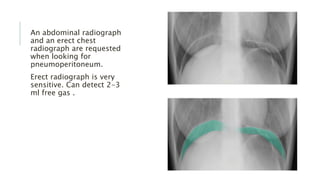

An abdominal radiograph

and an erect chest

radiograph are requested

when looking for

pneumoperitoneum.

Erect radiograph is very

sensitive. Can detect 2-3

ml free gas .